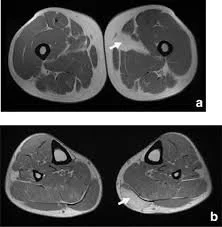

• Whole-body MRI and brain MRI using T1-weighted sequences

• AI-based quantification of:

• Total normalized muscle volume

• Visceral fat (deep abdominal fat around organs)

• Subcutaneous fat (fat under the skin)

• Brain age